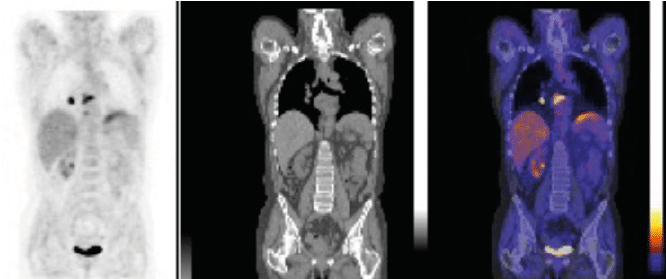

Each care team member can view PET/CT, PET/MR, SPECT/CT and conventional nuclear medicine studies in a uniform way that allows getting the most from the images.

SUV statistics offering standardization, choice of body weight, body surface area or lean body mass

Expandable list of dedicated color tables and thresholding

Triangulation and MIP display for PET and SPECT

PET, SPECT, CT

and MR hybrid imaging and fusion

Alpha blending